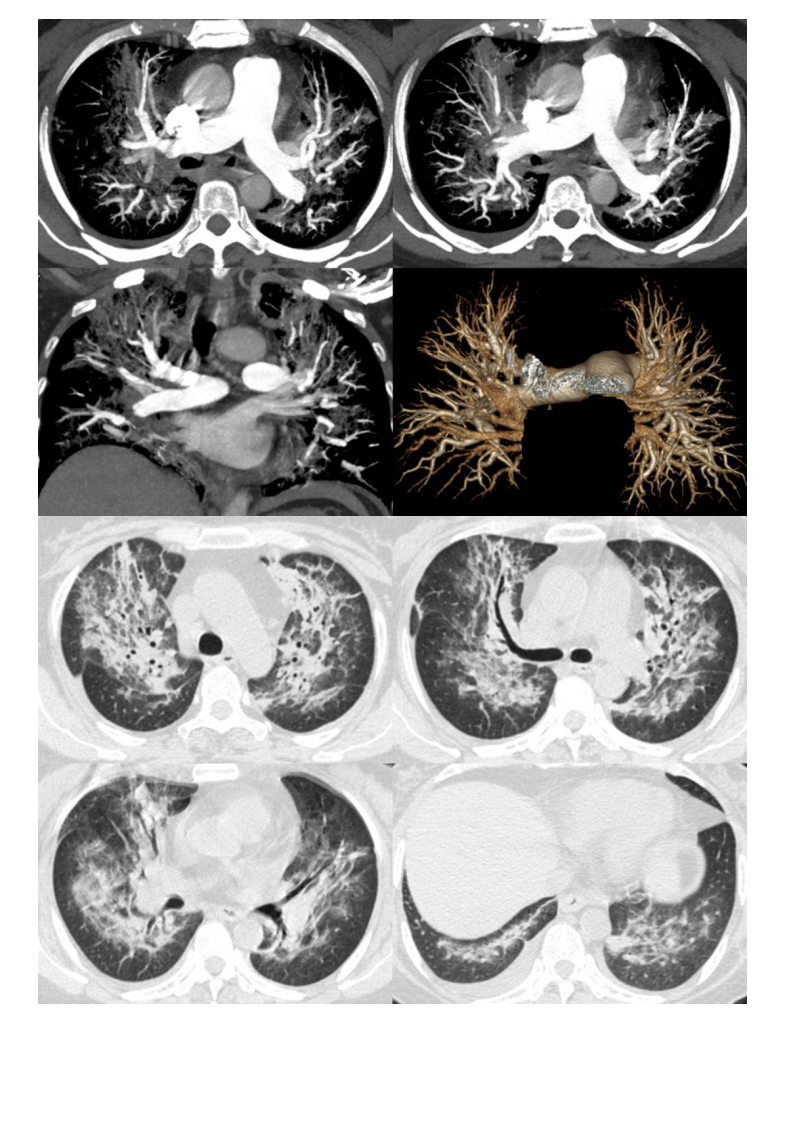

20210412_3【晨读结果公布】2021.04.12呼吸系统疾病——病例1:耶氏肺孢子菌肺炎(PCP);病例2:急性心源性肺水肿(ACPE).pdf